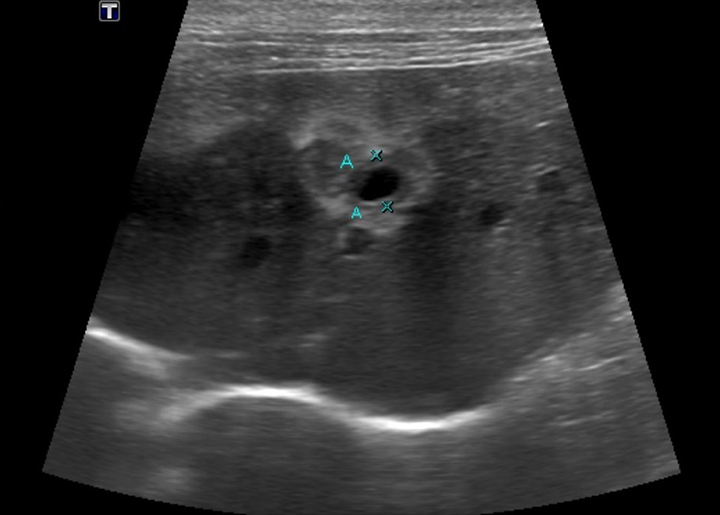

The Role of Imaging in Diagnosing Pancreatitis • MSPCAAngell Cat Pancreatitis And Constipation spot the signs of pancreatitis in cats and get expert advice on treatment, including recommended diets and treatment for feline pancreatitis. Pancreatitis happens when your cat’s pancreas becomes inflamed. what is pancreatitis, and how does it happen in cats? imaging is another important test for diagnosing pancreatitis in cats. It can be sudden and. Learn ways to. Cat Pancreatitis And Constipation.